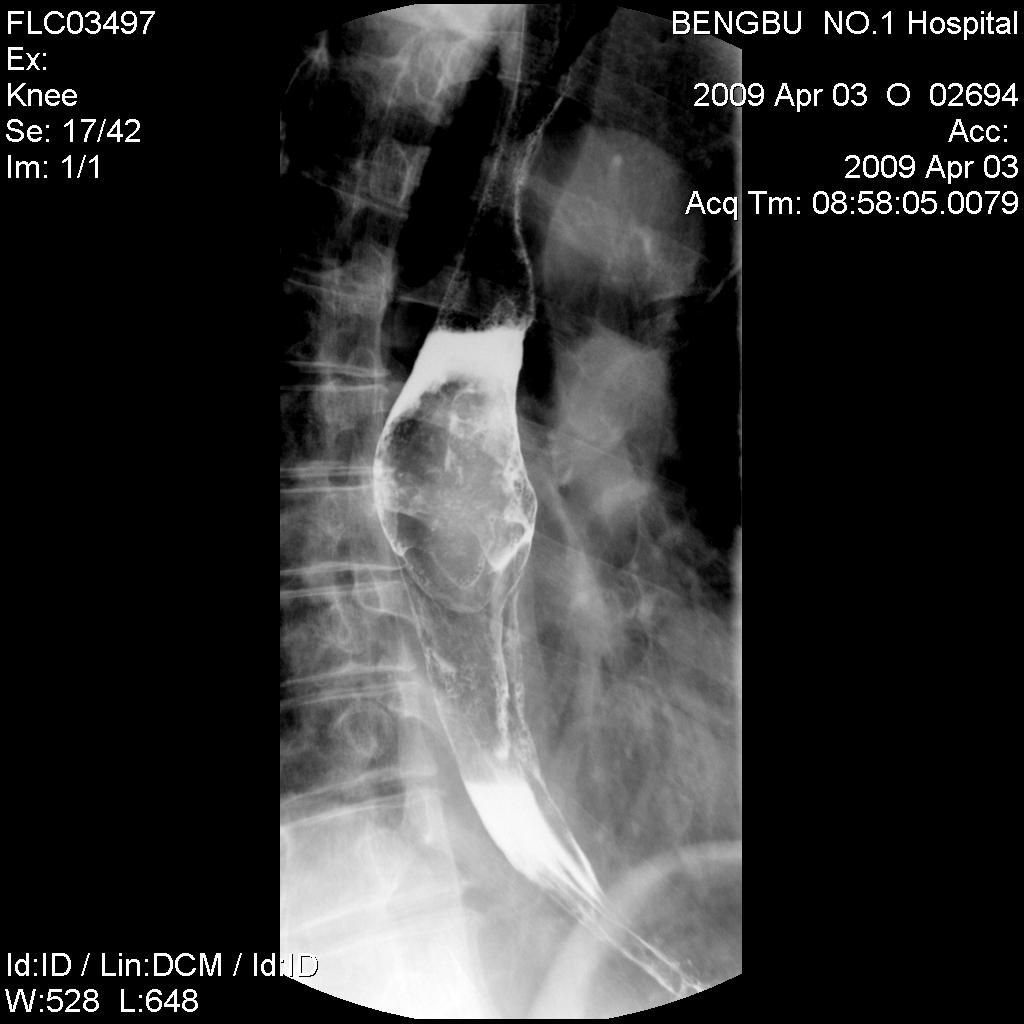

标题: X5565:男,50岁,吞咽阻塞感1月余。 [打印本页]

标题: X5565:男,50岁,吞咽阻塞感1月余。

食管中下段椭圆形充盈缺损,钡剂呈分流尚通畅,粘膜未见明显中断,其上段未扩张。初步考虑食管平滑肌瘤。曾有一病例影像表现类同,结果似为未分化癌。

食管中下段椭圆形充盈缺损,钡剂呈分流尚通畅,粘膜未见明显中断,其上段未扩张。初步考虑食管平滑肌瘤。

食管中下段椭圆形充盈缺损,边缘尚光滑,钡剂呈分流状通过块影,粘膜未见明显中断,管壁未见明显僵硬和缩窄改变。-----平滑肌瘤可能性大。

诊断:食管中下段椭圆形充盈缺损,边缘清晰光滑,肿块表面钡剂涂布征,似见细小龛影,钡剂分流改变,患段官腔扩张度及柔软度尚好,无明显僵硬及狭窄,上段以上食管未见明显扩张及钡剂储留,考虑食管平滑肌瘤,未除外溃疡性食道癌,建议食管镜活检。

肿块呈腔内膨胀性生长,边缘光滑

结果:食道癌。